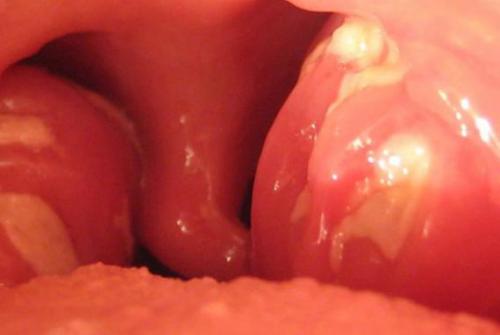

- Лакунарная, фолликулярная отличается более выраженными признаками интоксикации, когда температура достигает 39 градусов, беспокоят интенсивные болевые ощущения в горле, цефалгия, ломота в суставах, миалгия. При фарингоскопии визуализируются нагноившиеся фолликулы в виде зерен, в лакунах скапливается гнойное отделяемое. На поверхности миндалин появляется пленка.

Возбудителями могут стать как бактерии, так и вирусы, например, аденовирус. Этой разновидностью в основном страдают те, у кого были удалены миндалины. Основное проявление – это белый гнойный налет, который спустя несколько дней обволакивает всю полость рта.

По течению сильно напоминает предыдущий вид, но гной выделяется очами – в фолликулах миндалин, а не покрывает всю поверхность слизистой. Еще одно отличие – увеличение шейных лимфоузлов, боль при нажатии на них, из-за отека становится больно поворачивать голову.